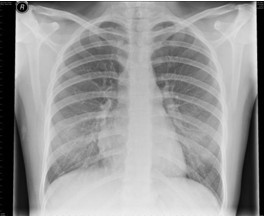

4.胸部X線檢查 哮喘發(fā)作時兩肺透亮度增加,呈過度充氣征象:并發(fā)肺部感染、肺不張、氣胸時出現(xiàn)相應(yīng)X線征象。

【題】下列哪項描述符合哮喘發(fā)作時典型的X線表現(xiàn)

A.兩肺透亮度增加,呈過度充氣征象

答案:本題選A。